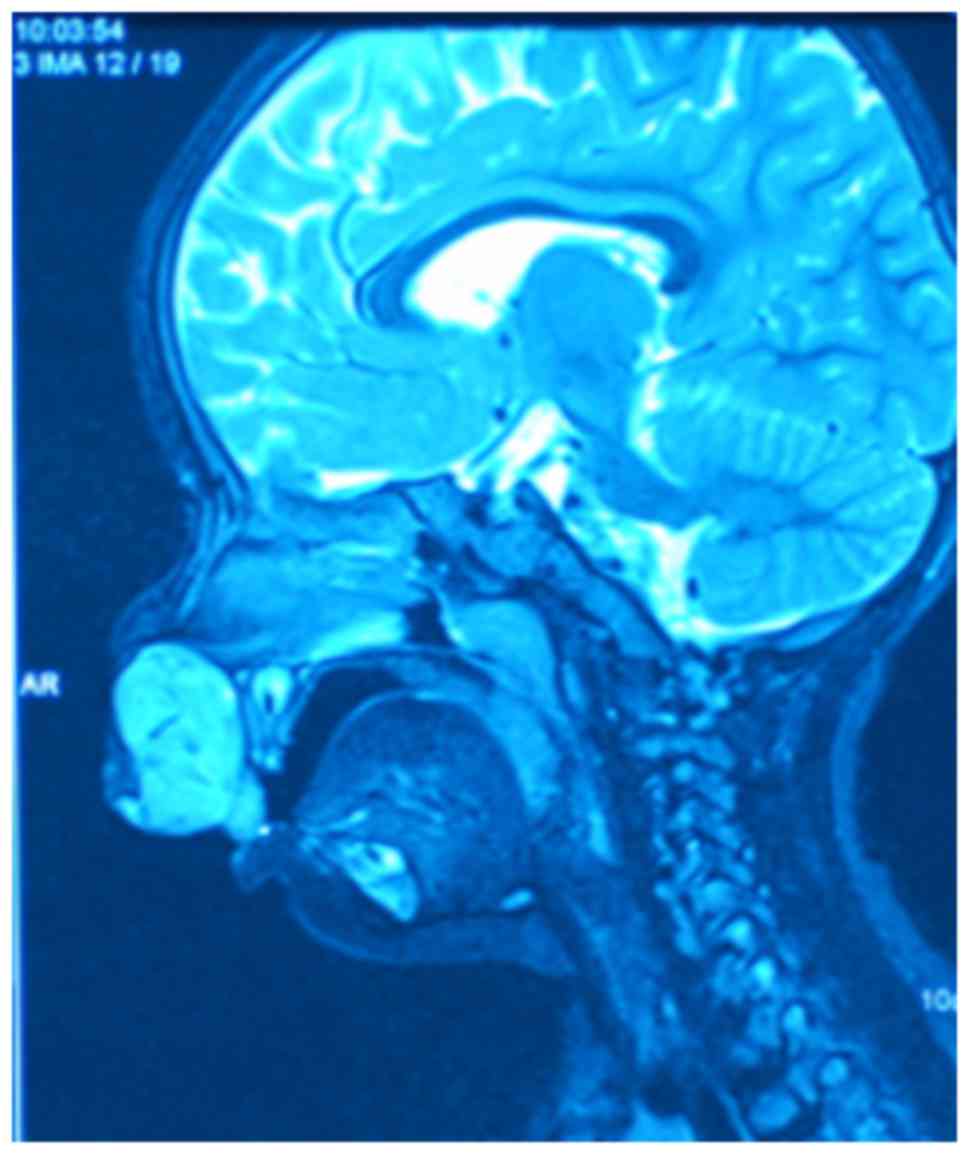

A 13-month-old female damaged her upper lip upon falling and the hematoma formed 2 months prior to admission to hospital. The patient underwent a hematoma puncture drainage at Juxian People's Hospital (Rizhao, Cina), but the mass recurred quickly. Upon examination, an exogenous reddish mass measuring 4×5 cm in diameter was revealed at the midline of the upper lip. The surface of the tumor was bleeding and scabby, as demonstrated in Fig. 1. Magnetic resonance imaging demonstrated a strong signal mass on the fat suppression imaging T2 weighted image in the upper lip with a clear border, as illustrated in Fig. 2. A biopsy sample was obtained from the fleshy mass under general anesthesia and the results confirmed the diagnosis of a YST. The biopsy sample was cut into pathological sections (4 µm thick). Certain pathological sections underwent hematoxylin-eosin staining (stained with hematoxylin-eosin at 60°C for 60 sec) and others underwent immunohistochemical staining with α-fetoprotein (incubated with anti-α-fetoprotein at 37°C for 2 h). Subsequently, the tissue sections were observed using a biological microscope at a magnification of ×400. Microscopic analysis revealed the characteristic reticular pattern and eosinophilic ball, as demonstrated in Fig. 3, Schiller-Duval bodies, as illustrated in Fig. 4, and immunohistochemical staining positive for α-fetoprotein (AFP), as demonstrated in Fig. 5. Laboratory screening revealed an AFP level >1,308 µg/l, with 1–30 µg/l being the normal range. Computerized tomography scans of the head, neck and thoracic regions and ultrasonography of the abdominal and pelvic areas demonstrated no signs of metastasis. Initial treatment comprised two cycles of Adriamycin (30 mg/m2, day 2,9), vincristine (1.5 mg/m2, day 1,8), cyclophosphamide (300 mg/m2, day 1–3) and cisplatin (90 mg/m2, day 1) (AVCP) chemotherapy and 1 cycle of ifosfamide (1.5 g/m2, day 1–5), etoposide (100 mg/m2, day 1–5) and vincristine (1.5 mg/m2, day 1,8) (IEV) chemotherapy. Subsequent to this regimen, the mass in the upper lip reduced to ~1×2 cm in diameter. The patient then underwent surgical resection. The biopsies of the resected area revealed only fibrosis, without any residual tumor tissue. The AFP level was measured subsequent to chemotherapy and resection, and exhibited a decline to within the normal range. After 36 months, there were no signs of recurrence or metastasis at follow-up examination.

Figure 2.

Magnetic resonance imaging demonstrated a strong signal mass on the sagittal section of the fat suppression T2 image in the upper lip with a clear border.